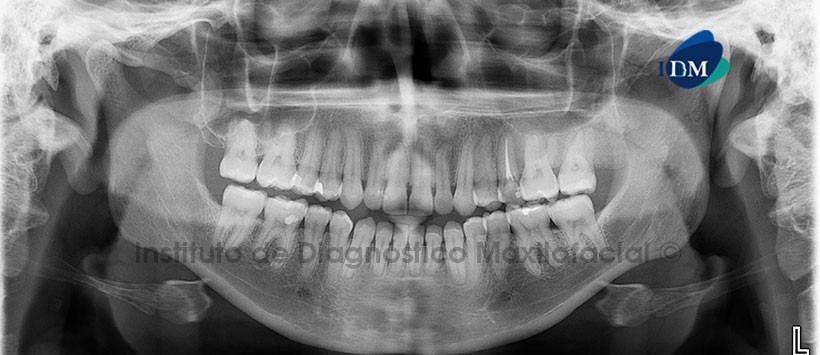

Paciente femenino de 14 años es referido al Instituto de Diagnóstico Maxilofacial por leve aumento de volumen de la región posterior del maxilar superior del lado izquierdo, no presenta sintomatología.

A la evaluación de la radiografía Panorámica (Figura 1) se observa imagen radiopaca en la región del maxilar superior izquierdo que se ex tiende desde la pieza 15 hasta la región de la tuberosidad y en sentido cefálico-caudal del reborde alveolar hasta el piso del seno maxilar; la lesión ocasiona la mimetización de la lámina dura y un aumento en el tamaño de la tuberosidad del maxilar.